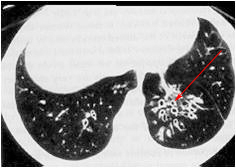

What is the pathology shown in this image?

bronchogenic carcinoma

What is the classification of this pathology?

neoplastic and malignant